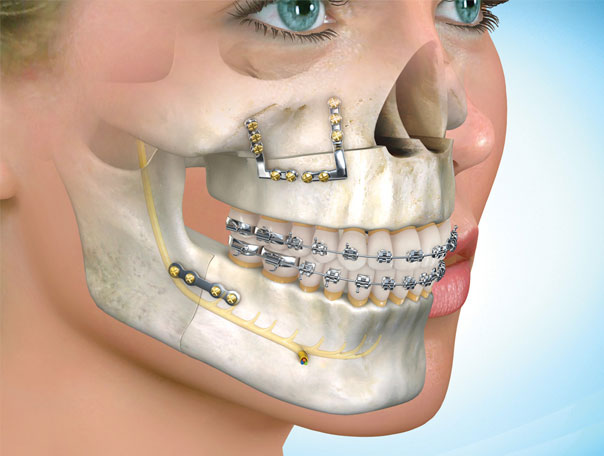

La Cirugía Ortognática se define como la cirugía de corrección de las deformidades dentofaciales que se realiza con la movilización del maxilar superior y la mandíbula en la mayoría de los casos, pudiendo ser combinadas con movilizaciones de mentón entre otros huesos faciales.

Su realización requiere de un estudio cuidadoso de cada cara, de un tratamiento en equipo entre el ortodoncista y el cirujano maxilofacial, y del soporte de la planificación mediante programas informáticos.

Estas intervenciones se practican bajo anestesia general. La corrección de la posición de los maxilares se realiza mediante incisiones intraorales (sin ninguna cicatriz facial). Se efectúa la osteotomía de uno o de los dos maxilares dependiendo de cada caso, y se reponen en la nueva posición fijándose con miniplacas. Esto permite una rápida recuperación de la intervención, con un ingreso hospitalario de uno o dos días, y una reincorporación laboral a los 10 -15 días. Se debe seguir una dieta blanda durante 30-40 días que se inicia el mismo día de la intervención.